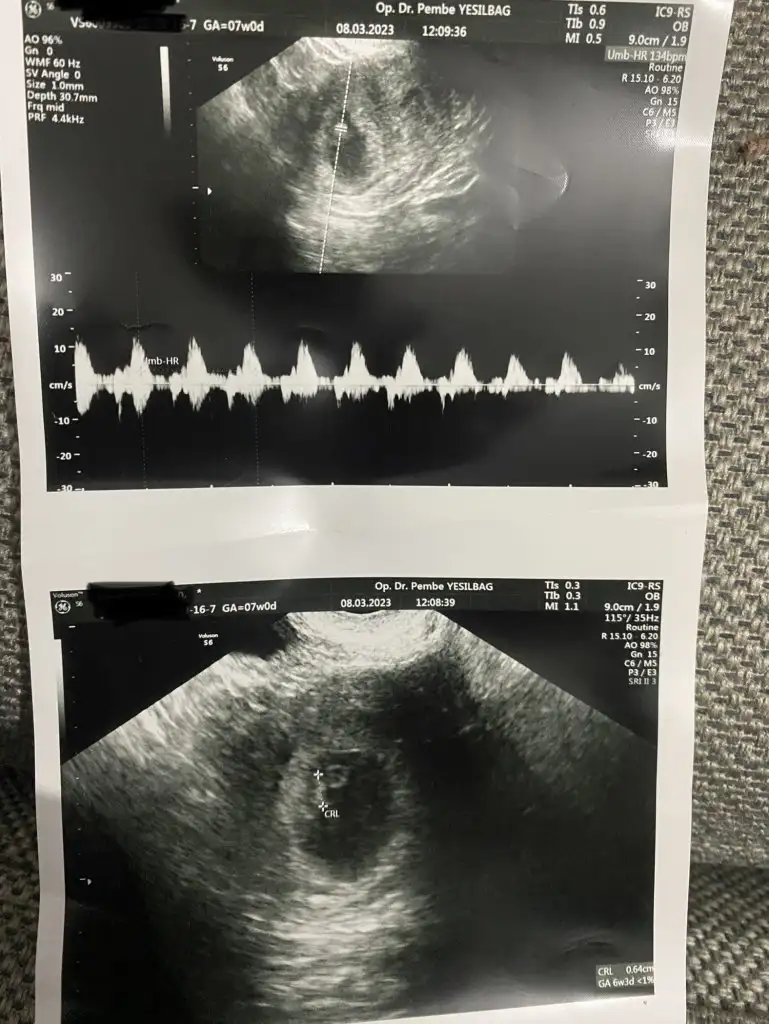

Bugün şu toxo sordum kızlar bir testi daha varmış oranına göre ilacı var dedi rabbime şükürler olsun biraz minnakız 7+0 olması lazım geç döllenme olmuş dedi bunada şükür hamdolsun resim koyarım pek gözükmüyoruz gerçi nefesimi tutarak kalbini duyduk Allah’ıma hamdolsun hepimiz sağlıkla kucağımıza alalım Rabbimin eli üzerimizde olsun